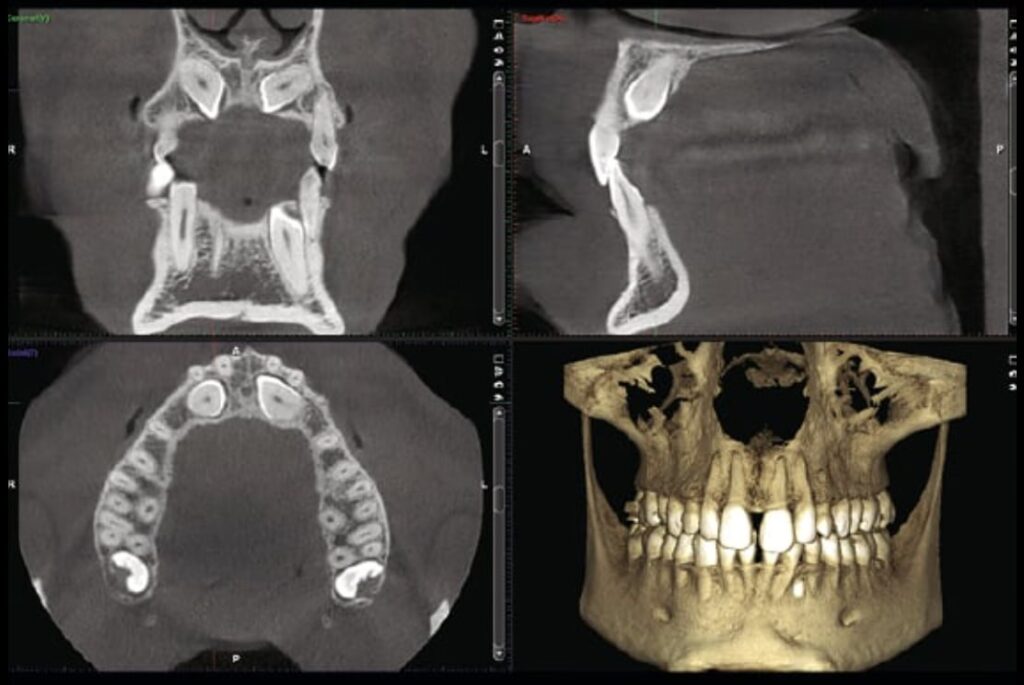

La CBCT (Cone Beam Computed Tomography) è un esame radiologico tridimensionale che consente di visualizzare le strutture anatomiche del cavo orale con una precisione non raggiungibile dalla radiografia tradizionale, utilizzando dosi di radiazioni contenute e modulabili in base al quesito clinico specifico.

La CBCT ricostruisce un volume tridimensionale del distretto esaminato: l’odontoiatra può navigare l’anatomia strato per strato, misurare distanze reali e non proiezioni, e identificare strutture che in due dimensioni resterebbero nascoste. Nel nostro studio utilizziamo il sistema CBCT Planmeca, che consente di selezionare il campo di vista (FOV) e i parametri di esposizione in funzione del quesito clinico specifico.